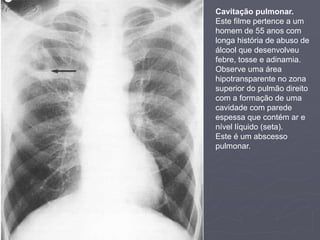

Cavitação pulmonar.

Este filme pertence a um

homem de 55 anos com

longa história de abuso de

álcool que desenvolveu

febre, tosse e adinamia.

Observe uma área

hipotransparente no zona

superior do pulmão direito

com a formação de uma

cavidade com parede

espessa que contém ar e

nível líquido (seta).

Este é um abscesso

pulmonar.